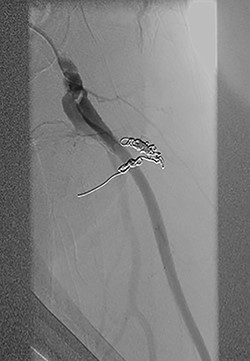

Vascular surgery was consulted and CT angiography demonstrated a large DFA pseudoaneurysm (Fig. 4A and B). Given her advanced years and comorbidities, a minimally invasive approach was recommended. The pseudoaneurysm was successfully embolized using numerous microcoils (Fig. 5). Completion angiography demonstrated complete occlusion of the pseudoaneurysm and patent superficial and DFA (Fig. 5). There were no immediate complications. After discussion with the patient, it was agreed that restarting her apixaban increased risk for her hematoma rebleeding and no anticoagulation was continued for stroke prevention.

(A and B): Frontal digitally subtracted angiography via a diagnostic catheter positioned in the proximal left DFA demonstrating a large pseudoaneurysm originating from a small DFA branch. The long, narrow and lobulated pseudoaneurysm neck can be see coursing along the cranial aspect of the pseudoaneurysm.

Postcoil embolization digitally subtracted angiography via a diagnostic catheter positioned in the left DFA demonstrating adequate embolization of the injured small DFA branch with complete exclusion of the pseudoaneurysm.